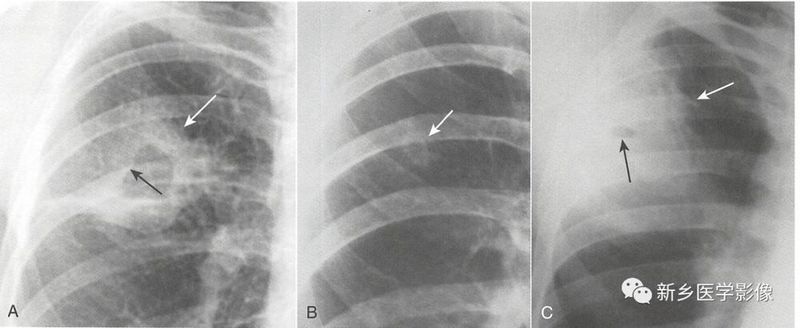

空洞

空洞的大小可从几毫米到几厘米。常位于肺实质内,是由于病变中心坏死形成的。

空洞壁是4种含气病变中最厚的,从3mm到几厘米不等。

3种最常见的肺空洞性病变,常常可通过空洞壁的厚度、内缘平滑度和壁结节鉴别。

A、鳞状细胞支气管肺癌形成的是厚壁空洞(白色实线箭头),内有壁结节(黑色实线箭头)。

B、肺结核空洞壁相对较薄,位于肺上叶,内壁光滑(白色实线箭头)。

C、葡萄球菌肺脓肿表现为特征性厚壁(白色实线箭头),该例患者空洞很小,且内壁光滑(黑色实线箭头)